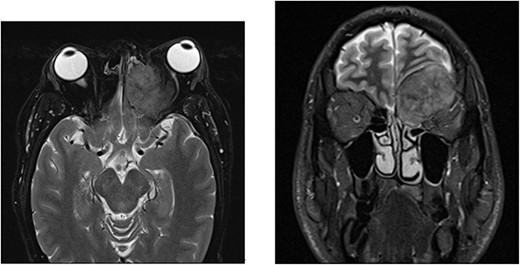

A 52-year-old male initially presented with preseptal cellulitis, which was successfully treated with antibiotics. One month later, he developed protrusion of the left eye with numbness over the left eyelid and ipsilateral forehead. No diplopia or signs of optic nerve compression were observed. A computed tomography (CT) scan revealed a large mass sized 36 × 31 x 29 mm centred over the left orbital roof, damaging bone and extending superiorly into the anterior cranial fossa, inferiorly into the orbit, as well as medially into the left olfactory and left nasal fossa (Fig. 1). It was reported as a sclerotic lesion with soft tissue elements. Another 25-mm lesion in the skull base infiltrated the right side of the clivus. These findings were confirmed by magnetic resonance imaging (MRI) of the head. The findings were then discussed at the Head & Neck multidisciplinary team meeting (MDT), where, considering the possibility that these might be metastatic deposits, an MRI was recommended to further characterize the lesion. It revealed extradural involvement of the left anterior cranial fossa without any evidence of intracerebral or leptomeningeal disease. Additionally, a thorax, abdomen, and pelvis CT with contrast showed multiple aggressive sclerotic lesions in the thoracolumbar spine and multiple nodules in the upper lobe of both lungs. No invasive mass in the prostate or abdomen, or inguinal lymphadenopathy was observed. Based on these findings, the MDT meeting recommended a transnasal tissue biopsy, which revealed an adenocarcinoma (Fig. 2). Immunohistochemical results were keratin positive, largely negative for CK 7 and 20, as well as negative for other markers, suggesting a prostatic origin. Prostate-specific antigen (PSA) marker test of the tumour cells was positive, indicating the prostate as the primary site.

Histological findings. (a) Respiratory epithelium showing infiltration by a tumour comprising cribriform sheets of relatively uniform rounded tumour cells with prominent nucleoli in keeping with adenocarcinoma. Morphological features along with immune profile (keratin positive, negative for CK 7 & 20) pointed to a prostatic primary. (b) Positive immunohistochemistry staining with PSA marker.